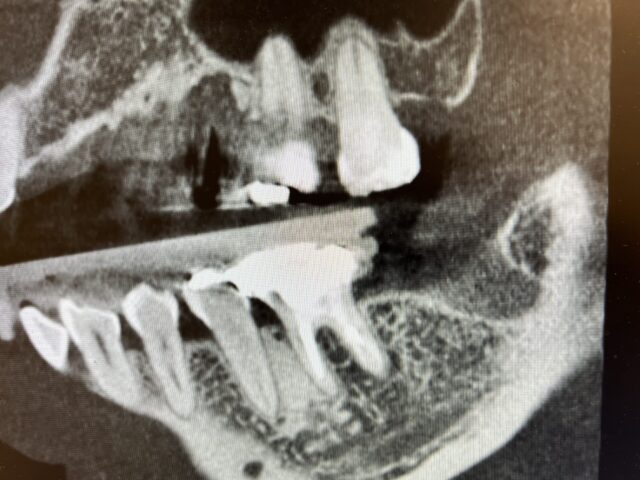

元々左下にブリッジが入っていましたが抜歯になってしまいインプラント治療を行うことになりました。

インプラント治療前の状態

インプラント治療後の状態